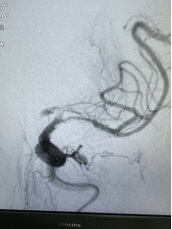

随即,卒中介入团队快速启动急诊手术流程。11:42,经介入治疗后,梁大爷闭塞血管顺利开通。再次造影显示,患者左侧大脑半球血流恢复。大脑在重新得到新鲜血液灌溉后,因缺血而不完全坏死的脑细胞逐渐恢复生机。